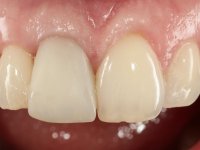

The treatment began with the placement of an intraradicular post and the creation of a new composite resin restoration. This procedure was performed with a surgical approach that allowed the remaining margins to be completely exposed, which were shown to be at a very infra-gingival level. Simultaneously, the periodontal pocket was curetted and root scaling and root planning of adjacent teeth were performed. Two months after this first intervention, the making of the crown began. A pre-print on silicone was performed to make a temporary crown with dual-cured composite resin. Gingival retraction was performed using the technique of kaolin paste compressed by the provisional crown. The impression was made using the double-mix technique with double viscosity with quick-setting silicone. In the laboratory, a crown with a ceramic-coated Zr infrastructure was made. The crown slightly overlapped tooth 12, allowing a dimensionally mimicry of the symmetrical tooth. Its fit was confirmed and approved by the patient; it was definitively cemented with resin-reinforced glass ionomer cement.